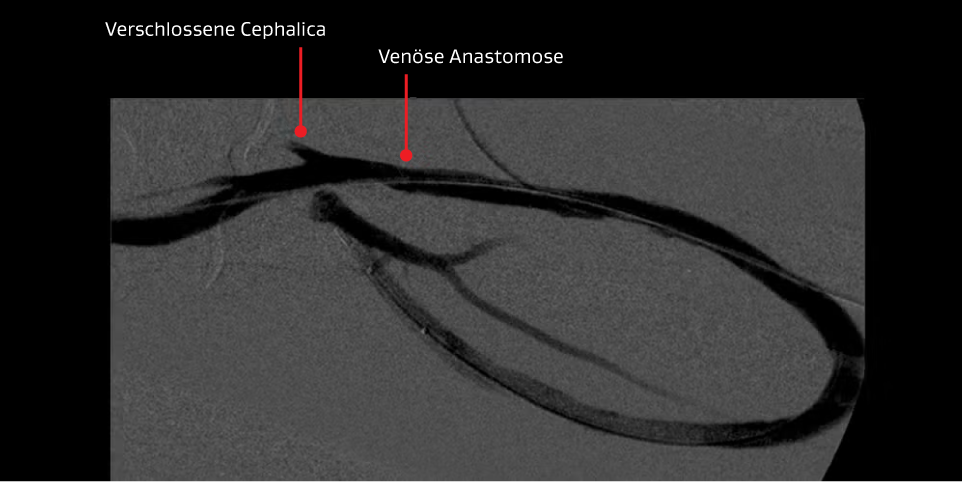

Dritte Intervention – Ein VIABAHN® Implantat wurde über den Ellenbogen hinweg platziert, um die rezidivierende schwere venöse Anastomosenstenose zu behandeln.

Verfahren mit dem VIABAHN® Implantat

- Das VIABAHN® Implantat wurde im Ellenbogen anstatt im versagenden Circuit platziert.

Ergebnisse:

- Die Angiografie lieferte ausgezeichnete Ergebnisse und der Blutfluss war wiederhergestellt.

- Durch eine präzise Platzierung war die Möglichkeit einer Fistel im Oberarm gegeben.

- Langfristig hat das VIABAHN® Implantat die wiederkehrenden Gerinnsel dieser Prothese behoben.

- Der Patient stellte sich zwischen Mai 2012 und Januar 2016 für 3 Interventionen (zwei PTA der Stenose und eine Thrombusentfernung) wieder vor, wobei zwischen den Interventionen durchschnittlich 414 Tage lagen.

Abbildungen mit freundlicher Genehmigung von Minneapolis Vascular Physicians. Verwendet mit Genehmigung.